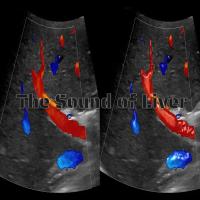

http://ultraliver.com